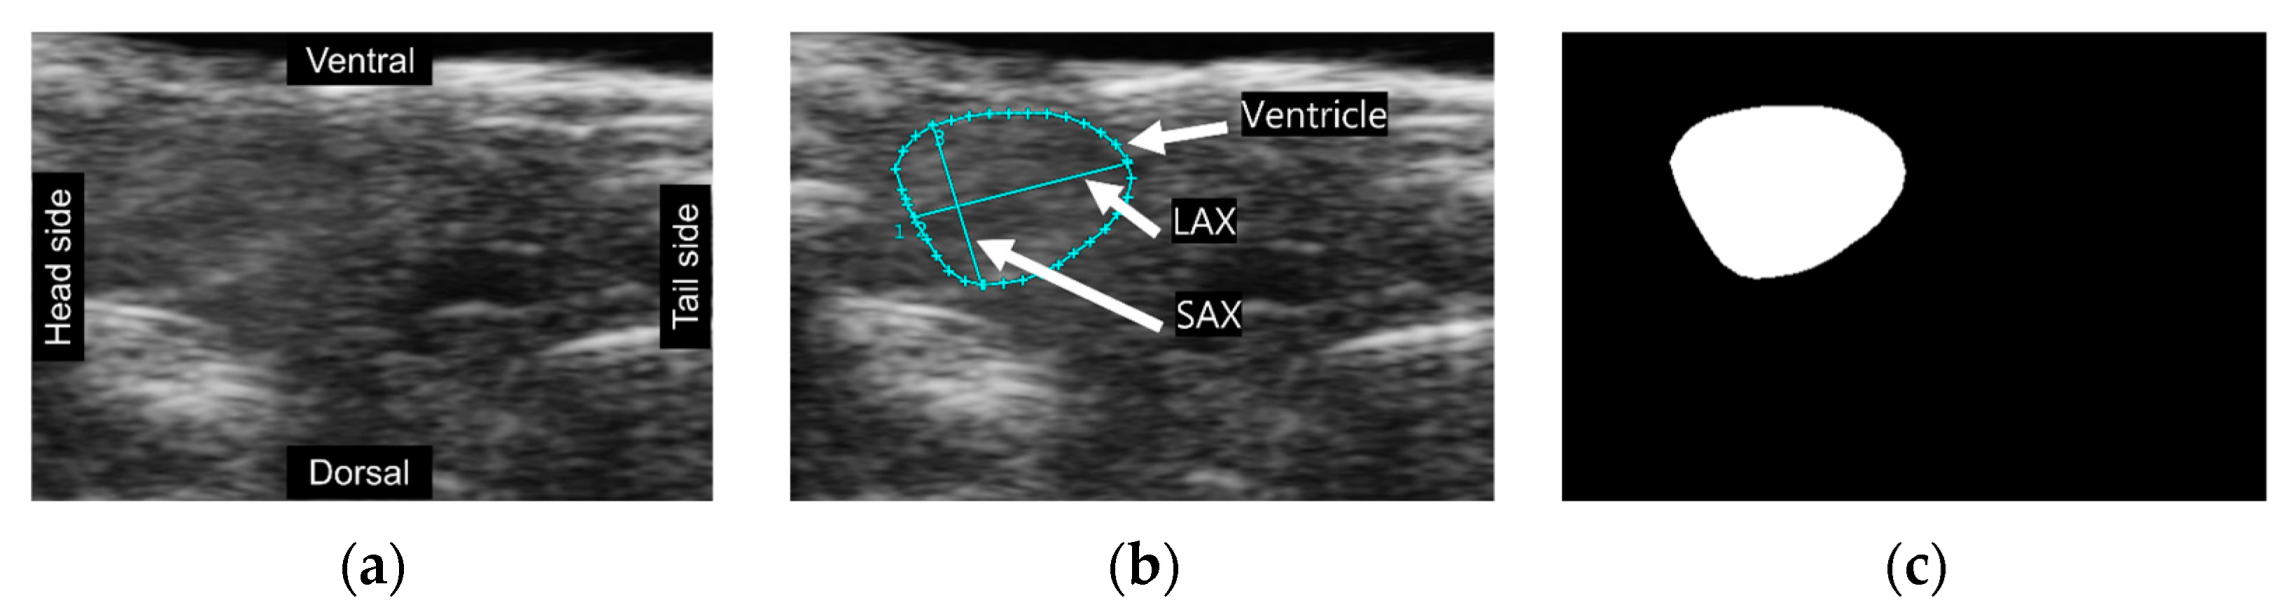

A total of 1005 frames were selected from 164 videos, with a range of 2 to 10 frames extracted from each video (Figure 1a). These frames underwent manual annotation using Vevo Lab software by our team member who is a well-trained biologist working in the field. The cyan lines in the image depicted ventricular boundaries, the long axis (LAX), and the short axis (SAX) of the ventricle (Figure 1b). Following the annotations provided, masks representing the ventricular area were produced through ImageJ software for training the image segmentation model (Figure 1c). We employed data augmentation methods, resulting in a four-fold increase in the dataset’s size. We utilized group k-fold cross-validation (k = 5) in data splitting and our model evaluation. Importantly, it was ensured that the validation set contained frames from videos distinct from those in the training set. This step aimed to avoid potential overfitting, wherein the model achieves high accuracy only by extracting features from familiar patterns and signal noise.

Figure 1.

(a) A cropped frame extracted from echo-videos; (b) A cropped image labeled by VEVOLAB; (c) A mask created by ImageJ and image processing method.